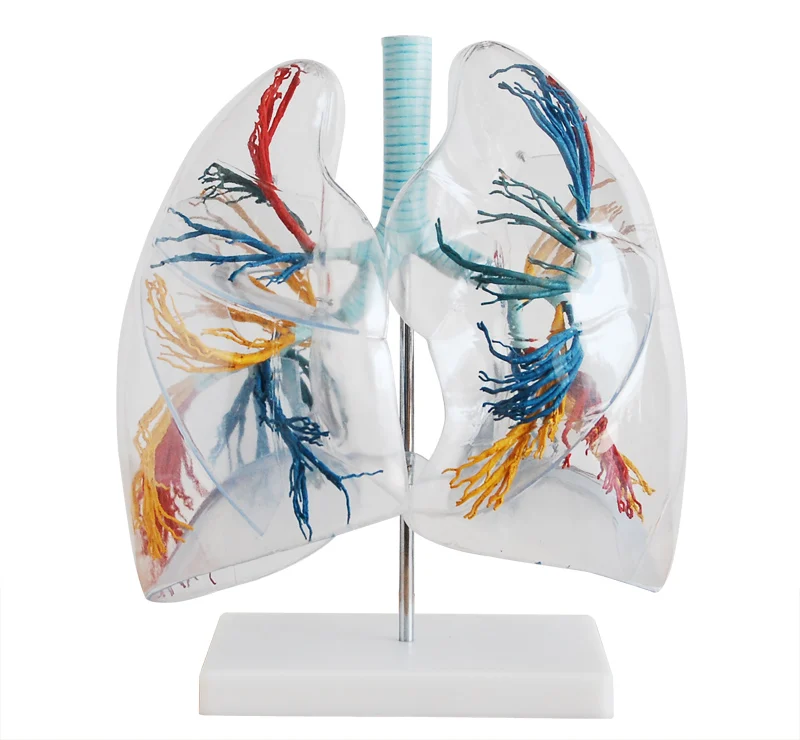

Анатомические изображения сегментов легких различных животных

Раздел: Другие животные